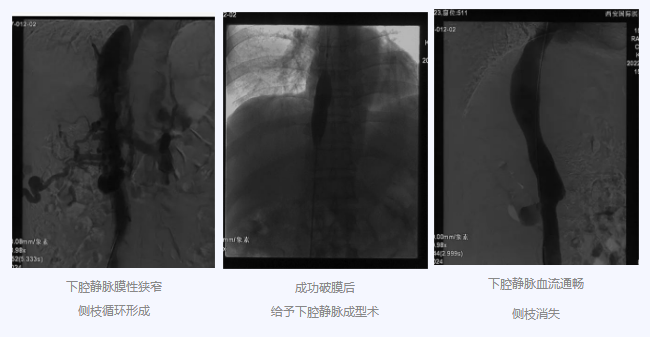

入院后,在韓國(guó)宏院長(zhǎng)的安排下,臨床經(jīng)驗(yàn)豐富的醫(yī)師給老謝做了B超、CT 等檢查,結(jié)果顯示:三支肝靜脈近心端閉塞,肝內(nèi)側(cè)枝循環(huán)形成,下腔靜脈近心房入口處隔膜樣狹窄,隨后的DSA血管造影也證實(shí):下腔靜脈狹窄,且有側(cè)枝形成,最終確診困擾老謝20年的疾病為混合型布加綜合征,是一種罕見(jiàn)病。

明確診斷后,韓院長(zhǎng)帶領(lǐng)團(tuán)隊(duì)縝密分析老謝的病情,為其制定最佳的治療方案,考慮到老謝的根本病因是下腔靜脈阻塞,介入手術(shù)成為首選治療方法,通過(guò)微創(chuàng)介入手術(shù),可準(zhǔn)確打通患者的閉塞血管,癥狀迅速緩解。做好充分術(shù)前準(zhǔn)備后,為患者行“下腔靜脈成型術(shù)”,精準(zhǔn)定位快速貫通,閉塞的下腔靜脈順利開(kāi)通,手術(shù)圓滿(mǎn)完成。